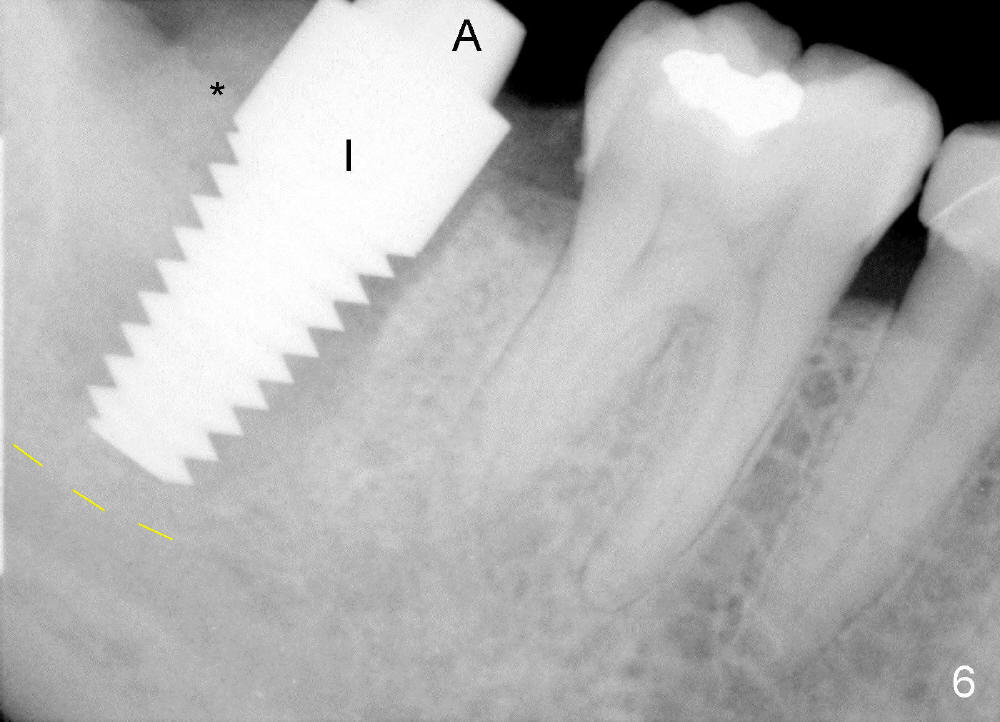

The tooth #31 of a 38-year-old lady has endo perio disease (Fig.1). Due to the large periapical lesion, there will be no solid (new) bone available for primary stability of an immediate implant (Fig.2: 7x17 mm). Yellow dashed line represents the upper border of the Inferior Alveolar Canal (IAC). Infiltration anesthesia is administered first. The mesiodistal widths of the root of the extracted tooth are 10 and 7 mm at the coronal and apical ends, respectively; the buccolingual ones 7 and 5 mm; the length 17 mm (Fig.3). The socket appears much larger than the root (Fig.4). To prevent paresthesia, no drills are used. Instead, a series of tap drills (6,7,8x17 mm) are sequentially inserted into the socket. The largest tap (Fig.5 T; 8x17 mm) binds to the socket securely with separation from IAC. Block anesthesia has to be administered before removal of the tap. A tapered implant (8x17 mm) is placed with insertion torque greater than 60 Ncm (Fig.6 I); allograft mixed with Osteogen is placed around the implant (*). Collagen dressing covers the opening of the remaining socket. The wound is protected with perio dressing, which is partially secured by an abutment (A in Fig.6). No paresthesia is reported by the patient a few hours postop.